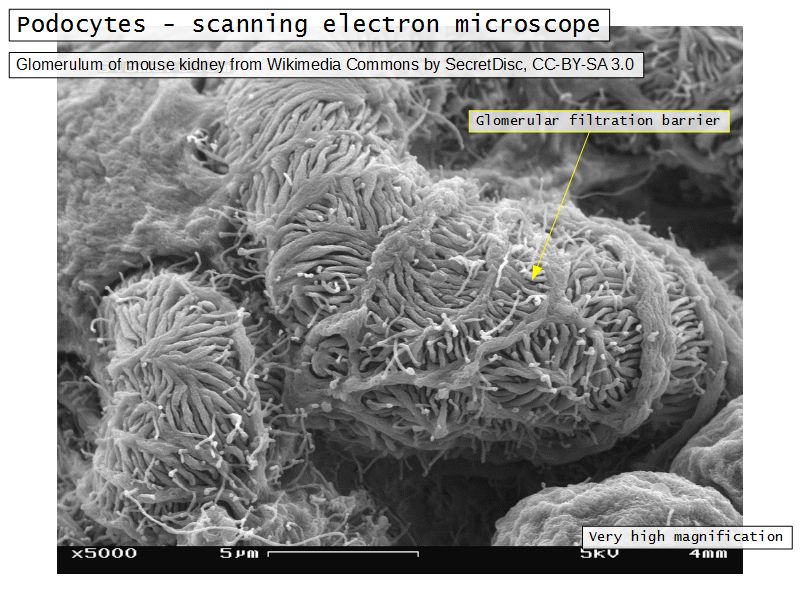

Glomerular filtration barrier

- Three layers

- Fenestrated epithelium

- Exclude blood cells & platelets

- Glomerular basement membrane

- Main filtration barrier

- Thick

- Fused epithelial & endothelial BM

- Replenished by podocytes due to removal by mesangial cells

- Glomerular epithelium

- Through filtration slit

Podocytes

- Visceral layer of epithelium

- Protrude into capsular space

- Attached to basement membrane

- Long cytoplasmic extensions

- Primary processes

- Secondary processes

- Podocyte feet

- Tightly spaced

- Filtration slits 20 - 30 nm wide